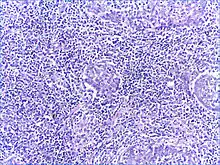

Histology

There is a marked lymphoplasmacytic infiltration. Lymphoid follicles surround solid epithelial nests, giving rise to the 'epimyoepithelial islands', that are mainly composed of ductal cells with occasional myoepithelial cells. Excess hyaline basement membrane material is deposited between cells, and there is also acinar atrophy and destruction.